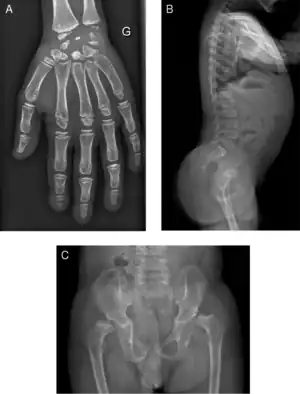

| Radiograph of a WRS child presenting with dysplastic bone growth in various regions of the body. | |

Wolcott–Rallison syndrome, WRS, is a rare, autosomal recessive disorder with infancy-onset diabetes mellitus, multiple epiphyseal dysplasia, osteopenia, mental retardation or developmental delay, and hepatic and renal dysfunction as main clinical findings. Patients with WRS have mutations in the EIF2AK3 gene, which encodes the eukaryotic translation initiation factor 2-alpha kinase 3.[1] [2] Other disease names include multiple epiphyseal dysplasia and early-onset diabetes mellitus.[3] Most patients with this disease do not survive to adulthood .[4] The majority of WRS patients die from fulminant hepatitis during childhood.[5] There are few reported cases for this disease. Of the 54 families worldwide with reported WRS cases, 22.2% of them are from the Kingdom of Saudi Arabia.[5] Of the 23 WRS patients in Saudi Arabia, all but one is the result of consanguineous marriages.[5] Another country where WRS cases have been found is Kosovo. Here, the Albanian population is also known for consanguineous marriages, but there were some cases involving patients from non-consanguineous parents that were carriers for the same mutant allele.[4]

Initially, patients with neonatal or early-childhood onset diabetes are possible candidates for having Wolcott–Rallison syndrome.[1] The other features include multiple epiphyseal dysplasia, osteopenia, intellectual disability, and hepatic and renal dysfunction.[1] Patients having features that suggest Wolcott–Rallison syndrome can be referred for genetics testing. The key way to test for this disease is through genetic testing for EIKF2AK3 mutations.[8] Molecular genetic analysis can be done for the patient and the parents to test for inherited or de novo mutations. It can also show whether the patient's parents are heterozygotes or homozygotes for the normal genotype.[4] X-rays can show bone age in relation to actual age. In typical WRS patients the bone age is a few years less than the chronological age.[4][5][9][10] Hypothyroidism is rare in WRS patients but can occur.[4]